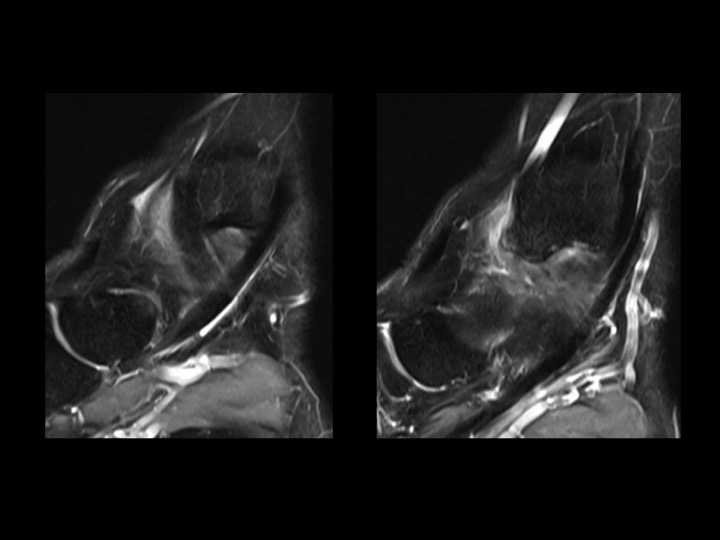

28M basketball injury 6mos ago with pain and tenderness in region of tibialis anterior at anteromedial ankle

This is an uncommon form of ankle impingement characterized by osteophytic spurring at the anterior medial malleolus and adjacent capsular/synovial proliferation and inflammation. The red arrow shows both in slide 1. There is a superimposed partial tear of the posterior (but not anterior) tibiotalar (deep deltoid) ligament, which is separate from this lesion. (note the normal tibialis anterior in slide 1) Reference article.

anteromedial ankle impingement